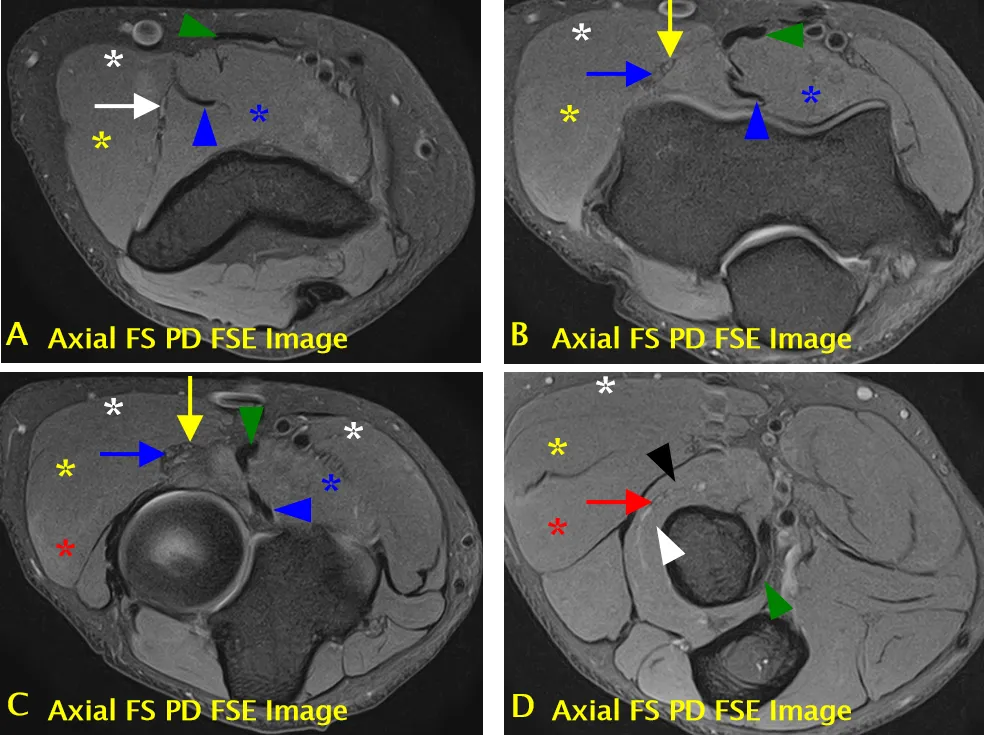

尺神经(黄色箭头标注);可见肱三头肌(长头)(A 中白色箭头标注)、指深屈肌(C 中黑色标注)、尺侧腕屈肌(肱骨头)(C 中白色标注)、尺侧腕屈肌(尺骨头)(C 中黄色标注)、尺侧腕屈肌(D 中红色标注)、指浅屈肌(C、D 中蓝色 * 标注);ME = 内上髁,OP = 鹰嘴

尺神经沟(骨纤维通道)结构

• 尺神经沟的底部由内侧副韧带后束和关节囊构成。

• 尺神经沟的顶部由尺神经沟支持带和尺侧腕屈肌筋膜深层(弓状韧带)构成。

内侧副韧带后束(蓝色箭头标注)、尺神经沟支持带(A 中箭头头标注)、弓状韧带(B 中箭头头标注)、尺神经(黄色箭头标注);可见尺侧腕屈肌(B 中黑色箭头标注)和共同屈肌肌腱(B 中白色箭头标注)。